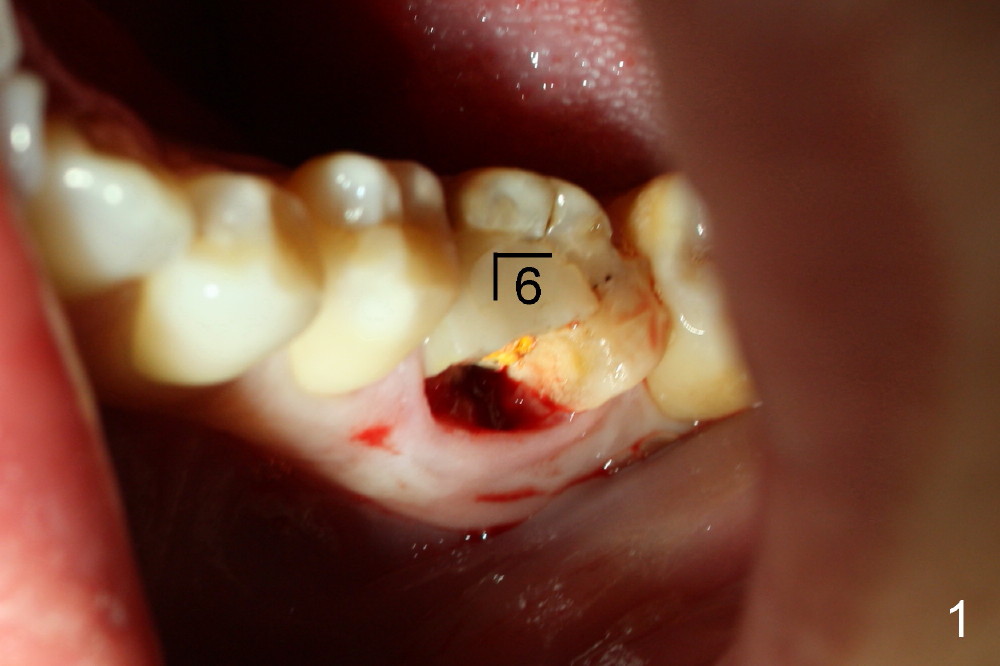

A 41-year-old lady fractures the crown of the lower left 1st molar (Fig.1.2). After removal of the remaining crown (Fig.3*) and exposure of the top of the septum, a pilot drill (D, 1.5 mm) is used to initiate the osteotomy. Drills with increasing diameters could be used to enlarge the osteotomy while the roots are in place (Fig.4: white rectangular outline).